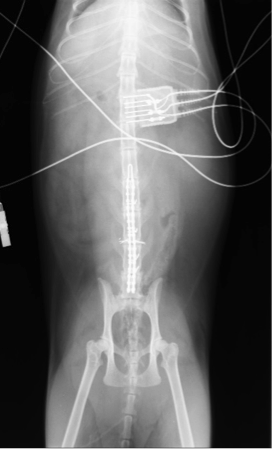

術後レントゲン

コメント;

術前に存在した腰椎間のずれは整復され、4本のφ0.7mmの田島式Kワイヤーとアリゲータープレートにて固定されています。